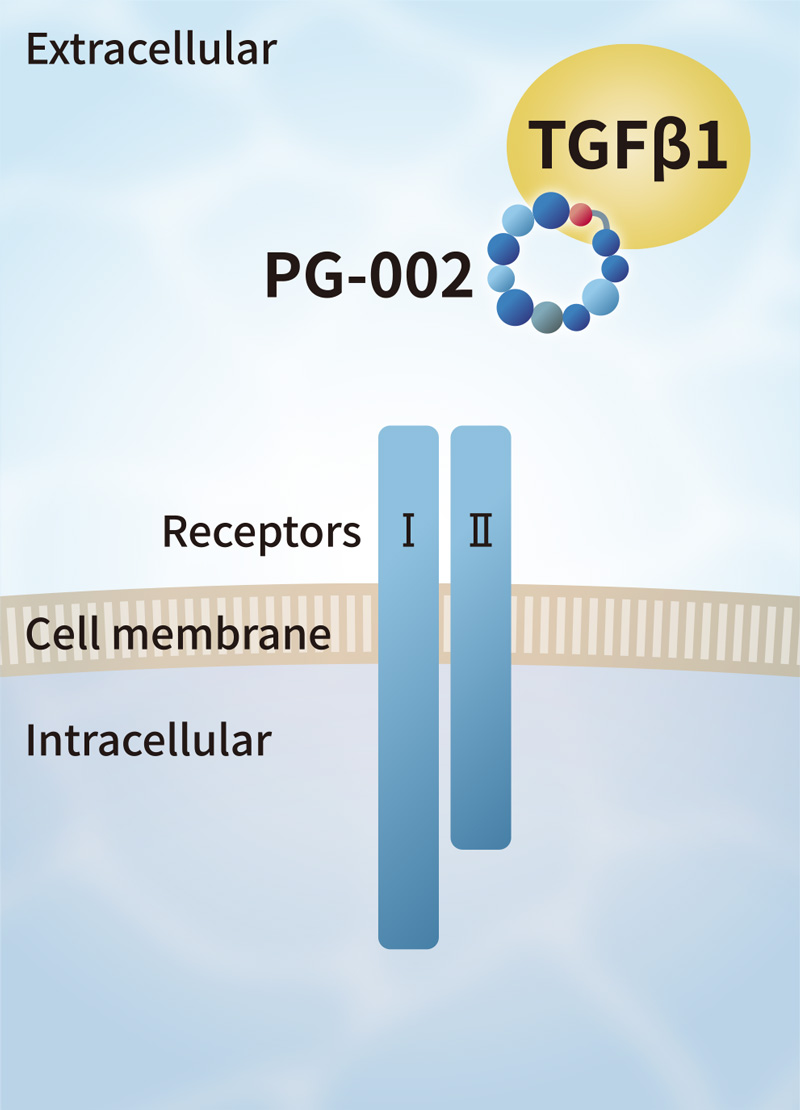

Solve challenges of conventional growth factors

Currently, FBS and recombinant growth factors are used for cell culture. However, such products have some challenges such as variation in quality among production lots, contamination by biological impurities, low stability, and extremely high prices.